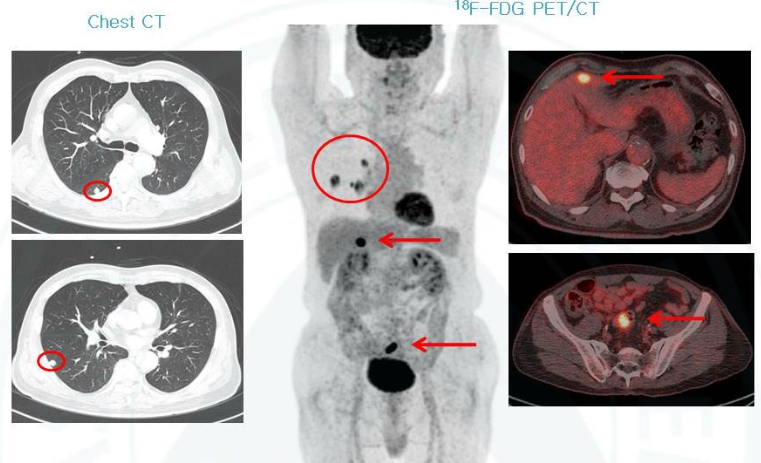

흉부ct로 볼수있는 질환 폐질환뿐 아니라 심장과 혈관, 흉막, 림프절, 뼈 구조까지 한 번에 보여줍니다. 폐렴, 결핵, 폐기종, 기관지확장증, 간질성 폐질환 같은 호흡기 질환은 기본이고, 폐에 생긴 작은 결절이나 혹도 세밀하게 확인할 수 있습니다. 폐암이나 전이암처럼 초기에 증상이 거의 없는 병은 CT로 발견되는 경우가 많아요.

흉부CT는 병이 있는지 없는지를 넘어서, 병의 진행 정도와 주변 장기 침범 여부까지 보여줍니다. 예를 들어 폐암의 경우, 5mm 미만의 아주 작은 결절까지 찾아내고, 종양이 혈관이나 기관지에 닿았는지도 확인합니다. 초기에 잡아내면 완치율이 크게 높아지죠.

| 종양·암 | 폐암, 기관지암, 흉막종양 | 작은 결절(혹)도 5mm 이하까지 확인 가능하며, 조기 진단에 도움을 줍니다. |

| 림프절 질환 | 종격동 림프절 비대, 전이성 림프절 | 암의 전이나 감염 여부를 파악하는 데 중요한 지표로 사용됩니다. |